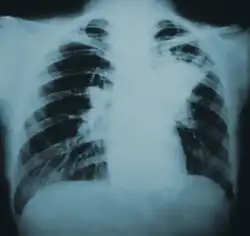

Blastomycosis is primarily a lung infection in about 70% of cases.[12] The onset is relatively slow and symptoms are suggestive of pneumonia, often leading to initial treatment with antibacterials. Occasionally, if a lesion is seen on X-ray in a cigarette smoker, the disease may be misdiagnosed as carcinoma, leading to swift excision of the pulmonary lobe involved. Upper lung lobes are involved somewhat more frequently than lower lobes.[12] If untreated, many cases progress over a period of months to years to become disseminated blastomycosis. In these cases, the large Blastomyces yeast cells translocate from the lungs and are trapped in capillary beds elsewhere in the body, where they cause lesions. The skin is the most common organ affected, being the site of lesions in approximately 60% of cases.[12] The signature image of blastomycosis in textbooks is the indolent, verrucous or ulcerated dermal lesion seen in disseminated disease. Osteomyelitis is also common (12–60% of cases). Other recurring sites of dissemination are the genitourinary tract (kidney, prostate, epididymis; collectively ca. 25% of cases) and the brain (3–10% of cases).[12]

Chest X-ray(lung infiltration) -